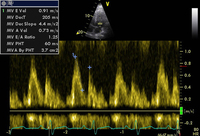

Pseudonormalização de fluxo de entrada mitral do E:A

Do acervo de Dr Jessica Webb; usado com permissão